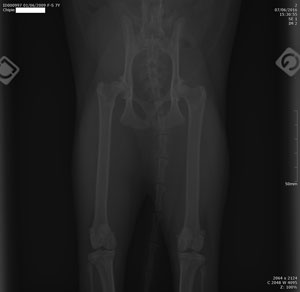

Le seul moyen de confirmer un diagnostic de dysplasie de la hanche est de réaliser une radiographie. Pour être interprétable, cette radiographie est très codifiée : le chat doit être allongé sur le dos, avec les pattes arrière maintenues bien parallèles. Une telle position est rarement acceptée spontanément par le chat, qu’il faut souvent tranquilliser ou endormir (anesthésie flash de quelques minutes).

Radiographie des hanches chez un chat.

Le vétérinaire examine ensuite sur la radio l’orientation des têtes de fémur par rapport au bassin ; il peut ainsi graduer la sévérité de la dysplasie. Il recherche aussi des signes de luxation ou d’arthrose, sous forme de proliférations osseuses autour de la cavité du bassin où s’insère la tête du fémur.